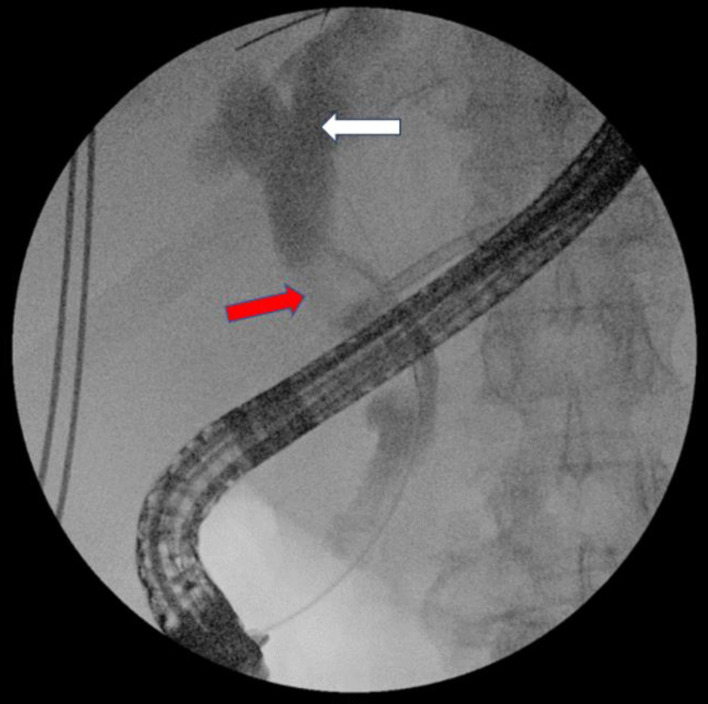

Endoscopic retrograde cholangiopancreatography (ERCP) is an important technique for treating biliary obstruction. A case report of a 75-year-old male with diagnosed choledocholithiasis and cholangitis was presented. He had a history of hepatic surgery 45 years ago, and during the ERCP, an unusual clinical scenario was encountered. Retained extraction basket during ERCP is a rare but known complication and there are no standard recommendations to manage it. To our knowledge, this is the first case report described in the literature with retention of an extraction basket in surgical sutures at ERCP and the longest period from surgery to stone formation in the biliary system. This case report aims to emphasize that in patients with a history of hepatobiliary surgery, postoperative material can cause complications during ERCP.